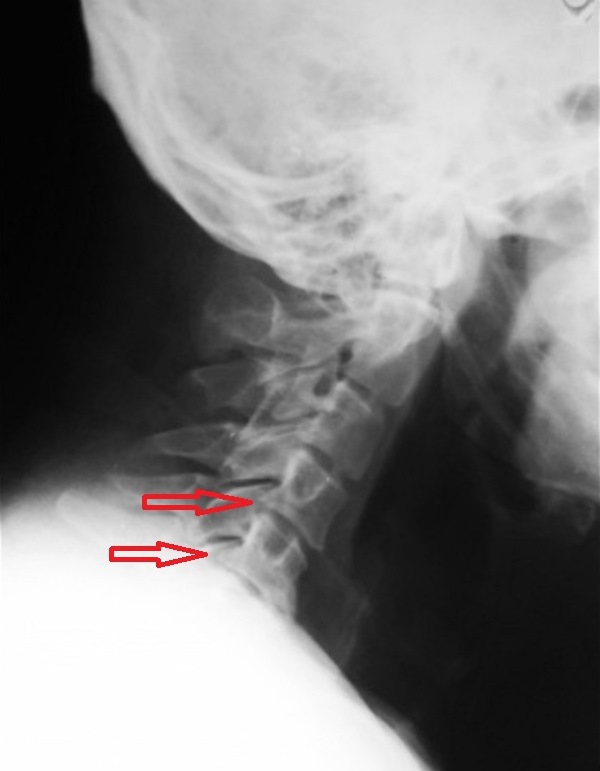

Для выявления деформации костных структур при остеохондрозе, полиостеоартрозе, спондилезе наиболее информативна рентгенография. Деструктивно-дегенеративные изменения хрящевых тканей, в том числе межпозвоночных грыж, а также связочно-сухожильного аппарата обнаруживают с помощью УЗИ, МРТ, КТ.